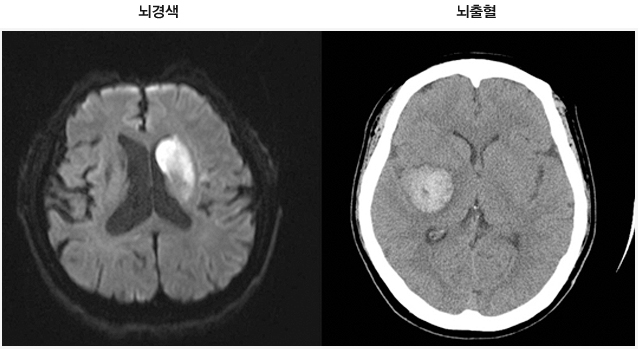

뇌경색이란 무엇인가요?

뇌경색은 뇌의 특정 부위에 혈액이 공급되지 않아 발생하는 문제입니다. 주로 혈관이 막히거나 좁아져 혈액이 제대로 흐르지 않을 때 발생하죠. 전 세계적으로 많은 사람들이 이 질환으로 고통받고 있으며, 특히 노인층에서 빈번하게 발생합니다. 뇌경색을 예방하고 조기에 발견하는 것이 중요한 이유는 이 질환이 뇌에 큰 손상을 줄 수 있기 때문입니다.